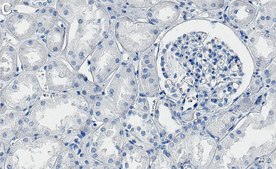

Immunohistochemistry (Paraffin) Analysis: A 1:1,000 dilution from a representative lot detected CD147 in human kidney tissue sections.